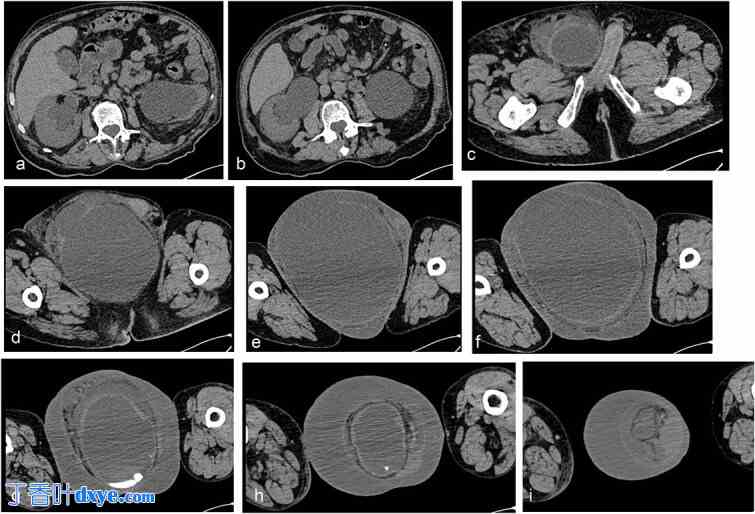

为评估触诊可及的右侧腹股沟肿块,进行了非增强骨盆计算机断层扫描 (CT)。 CT扫描显示右侧腹股沟区腱膜缺损,膀胱突出至右侧腹股沟管内,完全位于阴囊内。该发现与阴囊体积增大、阴囊周围脂肪呈条纹状以及阴囊壁增厚25 mm相关。同时观察到肾集合系统明显扩张,右侧直径为40 mm,左侧为62 mm,输尿管直径也增大。膀胱大小为240 × 173 × 194 mm,容积为4212 mL,完全充盈并位于右侧阴囊内。上述发现提示存在右侧腹股沟阴囊膀胱疝,伴双侧肾盂肾盏系统扩张,膀胱充盈可能加剧了这种情况(图3a-d、h和i)。

图 3.

简单的腹盆部 CT 扫描切片显示肾集合系统明显扩张,右侧直径为 40 mm,左侧直径为 62 mm,输尿管直径增大(a–c),右侧腹股沟区腱膜缺损,膀胱突出至腹股沟管内(d–f),膀胱完全充盈并位于右侧阴囊内(g–i)。